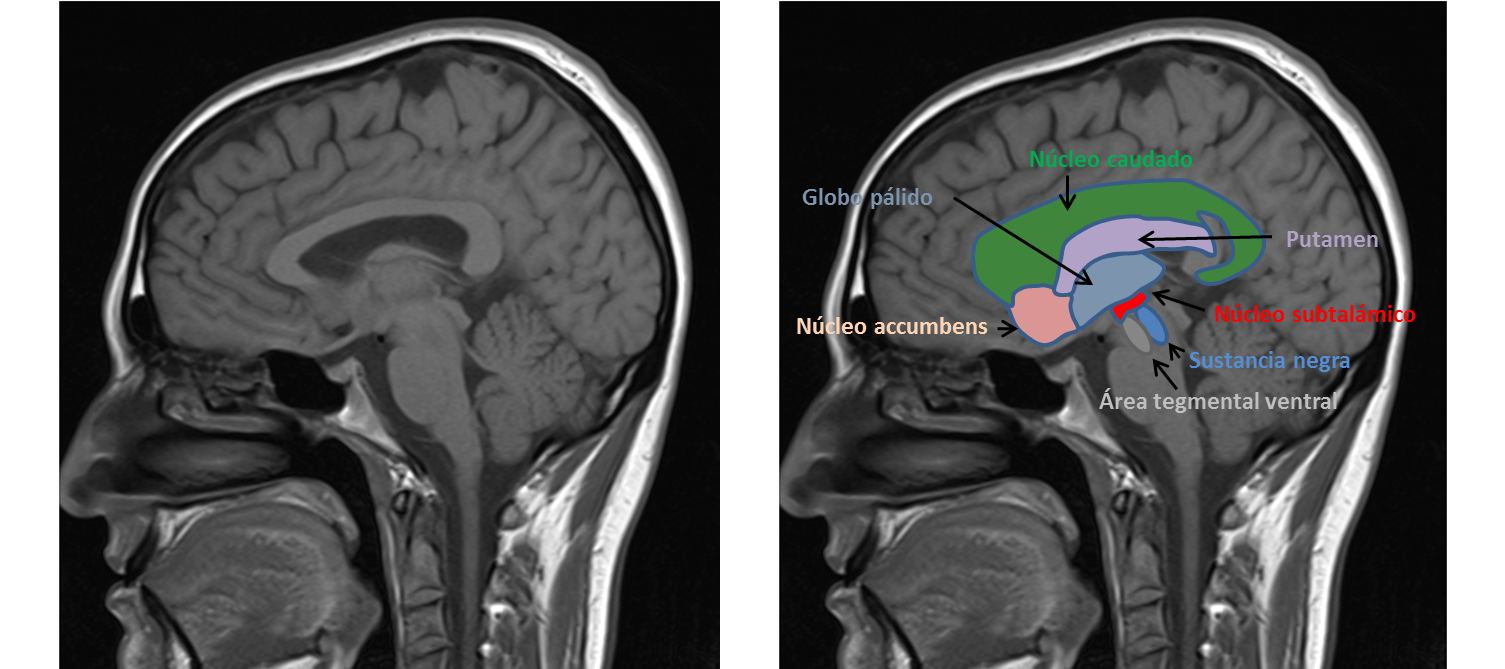

1. El sistema nigroestriatal que es el sistema que conecta el mesencéfalo con el cuerpo estriado (compuesto por el caudado y putamen) y el más afectado que produce los síntomas motores clásicos: bradicinesia, rigidez y temblor. La pérdida de neuronas dopaminérgicas en el mesencéfalo es selectiva. Las alteraciones patológicas son la pérdida de neuronas dopaminérgicas de la sustancia negra en la región central de la porción compacta (80-90%), menor en la porción tegmental central (40-50%) y mínima en la sustancia gris central (2-3%). Esta pérdida de neuronas en la región compacta es responsable del déficit de dopamina en las regiones dorsal y anterior del cuerpo estriado, estando más afectado el putamen que el núcleo caudado.

2. El sistema dopaminérgico extra- nigroestriatal, que a su vez se divide en tres partes:

2.1. Aquel sistema que se origina en el mesencéfalo y se dirige a estructuras diferentes al cuerpo estriado: el sistema dopaminérgicos mesolímbico, mesocortical y mesopálido.

La vía mesolímbica se proyecta hacia áreas cerebrales límbicas y se relaciona con alteraciones del ánimo. La vía mesocortical se dirige a la corteza cerebral y se relaciona con alteraciones cognitivas y la vía mesopálida conecta el globo pálido y se relaciona con las alteraciones motoras.